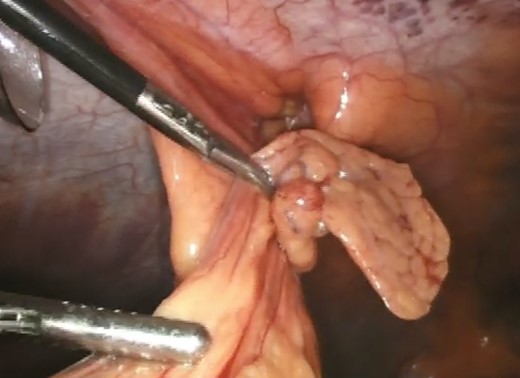

Upon successful reduction (Fig. 4), the hernia neck was closed laparoscopically with an intra-corporeal V-loc™ suture (Fig. 5). Closure of the hernia neck creates muscle apposition thus allowing for effective functioning of the abdominal wall musculature (Fig. 5). We extrapolated this data from incisional herniorrhaphy and the component separation technique [4]. The hernia defect was then covered with an underlay Ventralite™ mesh and secured with Absorbatac™ staples (Fig. 6). The Ventralite™ mesh is a dual layer mesh with one side consisting of an absorbable hydrogel barrier facing the bowel which reduces the risk of bowel adhesions. Her post-operative recovery was uneventful and she was discharged home the same day.

The hernia was repaired laparoscopically through a TAPP mesh repair. Laparoscopic visualization revealed a small umbilical hernia as well as a falciform ligament port site hernia (Fig. 7). The falciform ligament was mobilized and the hernia was reduced into the abdominal cavity (Fig. 8). The peritoneum around the hernia neck was mobilized to clearly expose the neck. The neck was then closed intra-corporeally with an intra-operative V-loc non-absorbable suture™ (Fig. 9). The hernia defect was then covered with an underlay Ventralite™ mesh and secured with Absorbatac™ staples (Fig. 10). The umbilical hernia was not repaired as we had not obtained consent for its repair. This was an intra-operative diagnosis. Her post-operative recovery was uneventful and she was discharged home the same day.